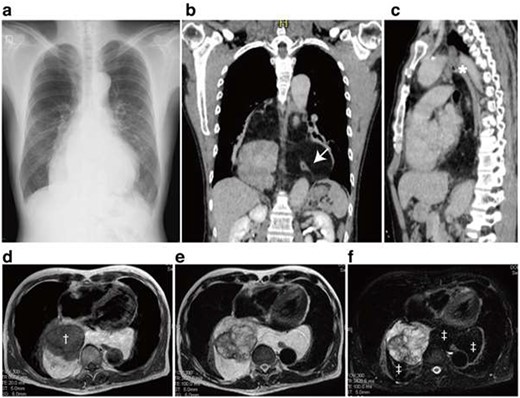

A 57-year-old man was referred to our hospital due to an abnormal chest X-ray. His previous history included hypertension and subcortical intracerebral hemorrhage that was conservatively followed up without surgery. Chest X-ray demonstrated an enlarged mediastinum without loss of cardiac and diaphragmatic outlines (Fig. 1a). Computed tomography revealed a giant posterior mediastinal tumor composed of a well-circumscribed solid compartment with small calcifications, encapsulated by a fat-density compartment (Fig. 1b). The tumor extended longitudinally from the aortopulmonary window to the level of the diaphragm (Fig. 1b and c). The heart was deviated anteriorly by the tumor; however, the patient had no cardiac symptoms. The esophagus was completely involved in the fat-density compartment (Fig. 1b). Magnetic resonance imaging also indicated that the solid mass was surrounded by a fatty compartment (Fig. 1d–f).

Chest X-ray, computed tomography and magnetic resonance imaging. A Chest X-ray demonstrated enlarged mediastinal shadow (a). Axial section revealed a posterior mediastinal tumor displacing the heart anteriorly (b). The well-capsulated tumor expanded into both thoracic cavities and involved the esophagus (b, Arrow). The superior border of the tumor reached the aortopulmonary window (c, asterisk). Magnetic resonance imaging of the tumor revealed the heterogeneous components in the tumor where a T1-low intensity component (†) was surrounded by fat components (‡) (d–f). T1-weighted image (d), T2-weighted image (e) and Fat-suppressed T2-weighted image.